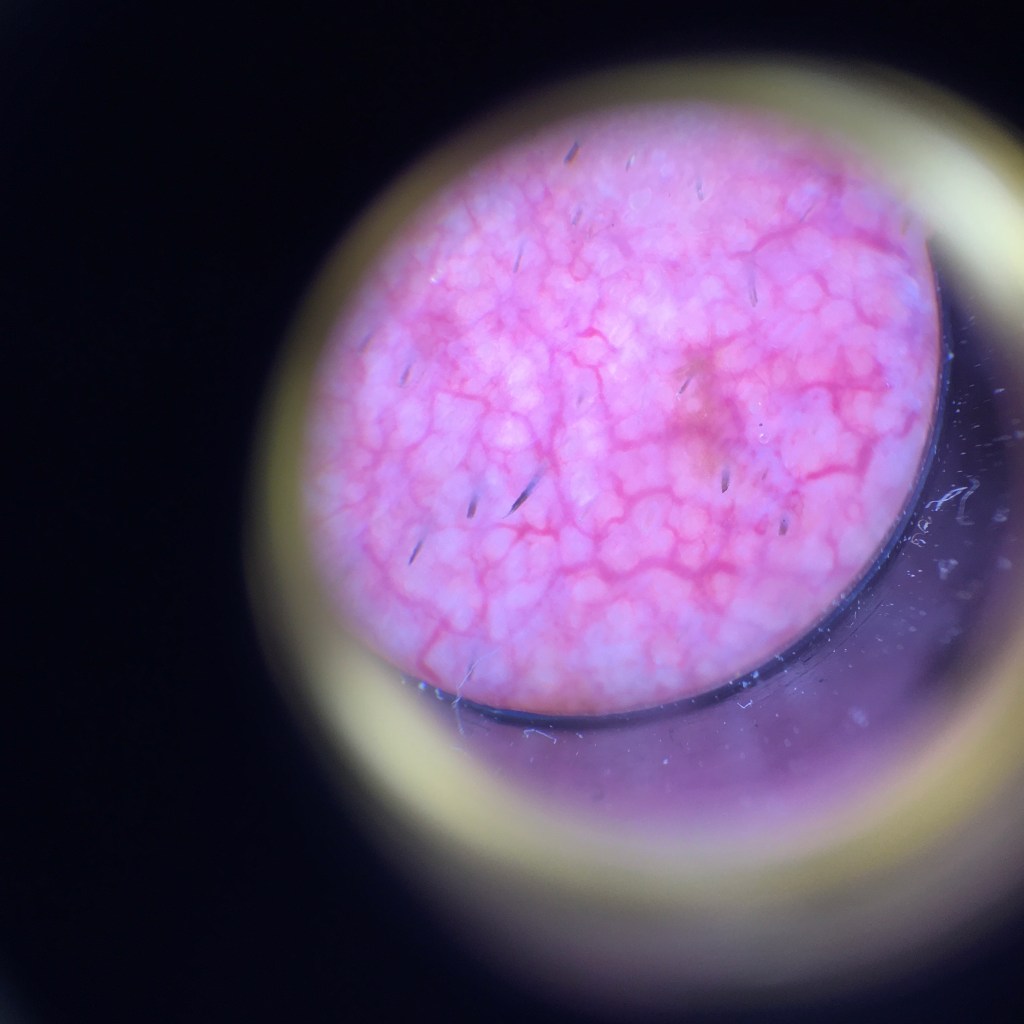

On Thursday, in a small meeting room at work, windows blanked out with sheets of brown paper, I stripped down to my underwear. Time for my annual check up so that my moles could be checked for abnormalities that may indicate skin cancer. This picture from the right side of my face was taken through a dermatoscope that will result in a non urgent trip to the GP.